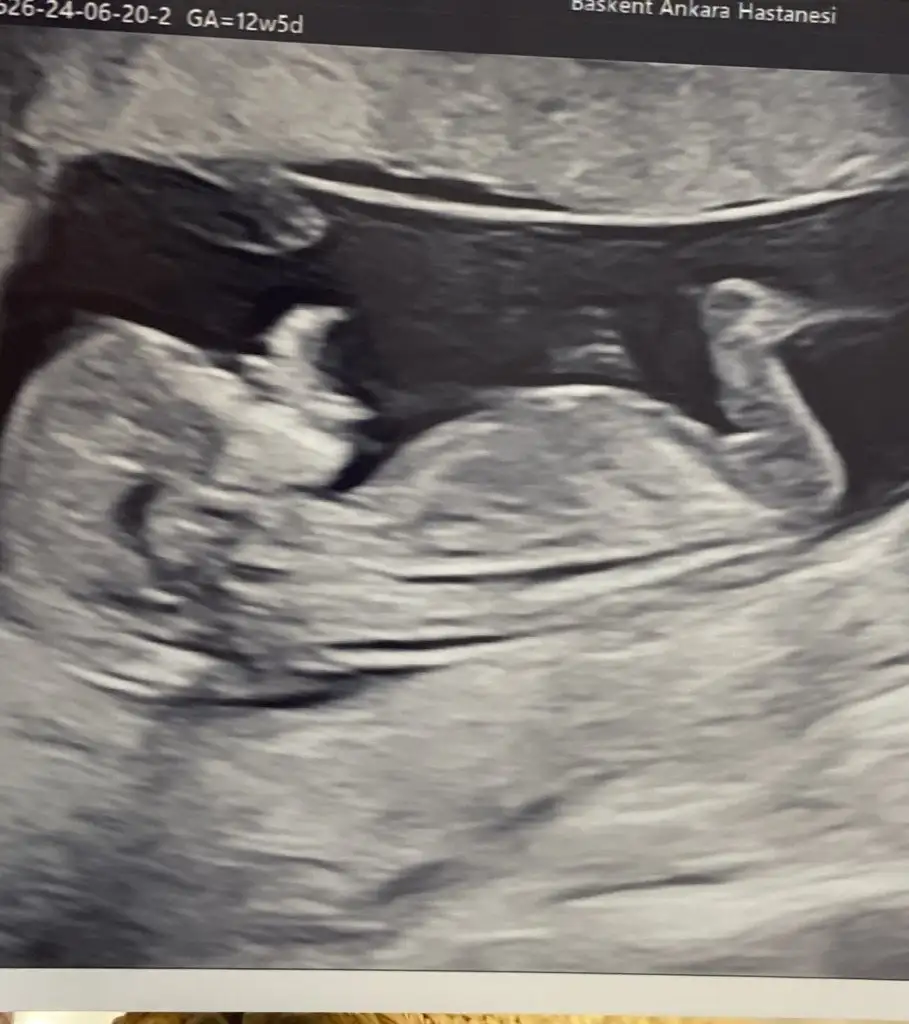

Kız galibaselam kızlar, kontrolümüz vardı bugün 12+5 deyiz. burun kemiği, ense ölçümleri gayet iyi. ikili yapmadık nipt testi yaptıracağımız için. kan verdik 10 güne çıkacak. cinsiyet tahmininiz varsa alırım